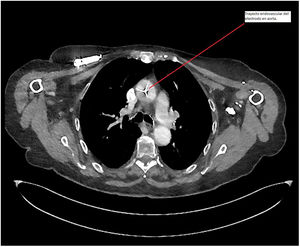

Dado los hallazgos, se decide realizar una tomografia computarizada que confirma la inserción del cable de marcapasos endocavitario, vía arteria subclavia derecha con trayecto transaórtico (fig. 3) y con extremo distal alojado en ventrículo izquierdo.